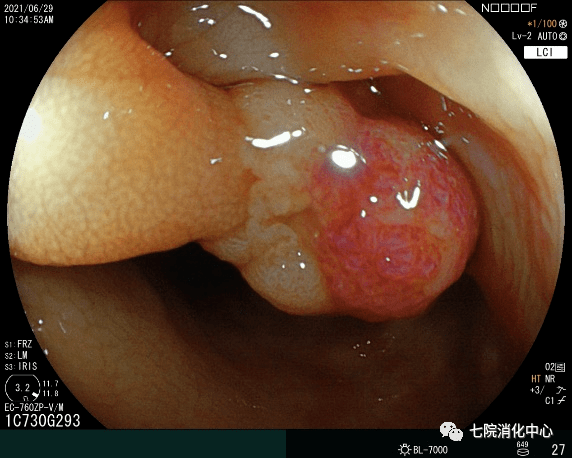

肚子不舒服 , 大便带血 , 排便习惯改变…… 65岁的王阿姨前段时出现的这些症状 可吓坏了她 , 于是来到西 安市胸科医院消化中心就诊 , 接诊的消化科副主任张蓉在了解其病情后 , 将其收治入院 。入院后肠镜检查发现 , 其肠道内多发大小不等息肉 , 最大直径1.8cm 。医生当即对息肉进行了切除处理 ,病理提示管状绒毛状腺瘤伴低级别上皮内瘤变—一种结肠癌的癌前期病变, 但庆幸的是发现较早 , 不然这个息肉很可能已经变成结肠癌 。目前王阿姨已经康复出院 , 之后只需要每半年复查一次肠镜 。